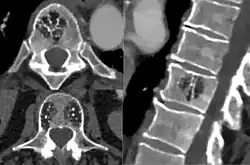

Для диагностики младенческих гемангиом достаточно пройти консультацию у специалиста, занимающегося лечением данной патологии и сделать УЗИ. Выполнение КТ, МРТ, ангиографии выполняется в редких случаях, когда затруднительно установить точный диагноз или при подозрении, например, на наличие образований в просвете гортани.